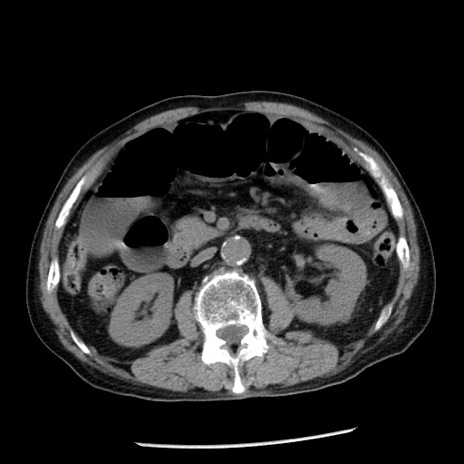

症例26(横断像)

【症例】80歳代男性

【主訴】嘔吐

【現病歴】昨晩2回嘔吐あり、今朝になっても嘔吐あり。来院。

【既往歴】胃潰瘍

【身体所見】意識清明、BT 37.6℃、BP 166/95mmHg、HR 100bpm、SpO2 97%、腹部:平坦・軟、腸蠕動音聴取良好、圧痛なし。

【データ】WBC 21900、CRP 1.46